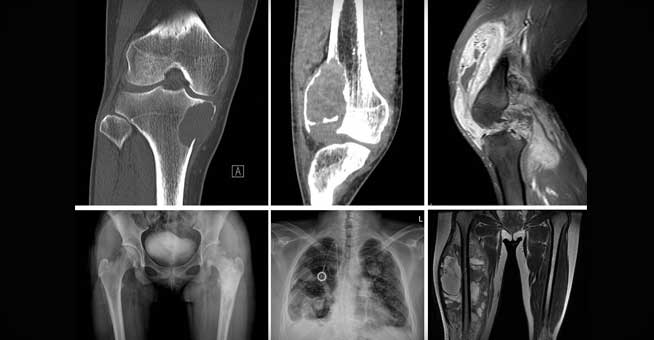

병기결정을 위해 시행하는 검사는

X-ray(가장처음), MRI, bonescan, chest CT, PET-CT, biopsy(마지막 검사) 등이 있습니다.